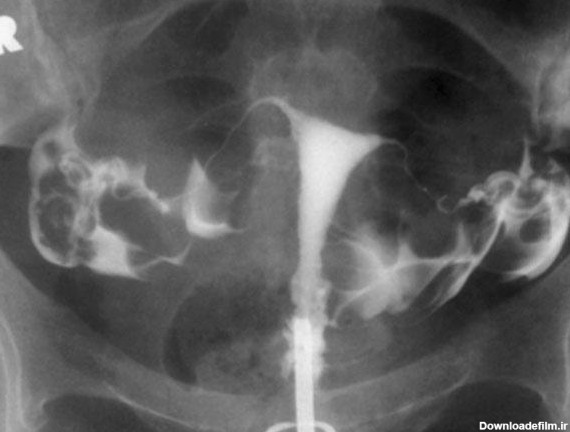

عکس رنگی رحم یا هیستروسالپنگوگرافی روشی است که به منظور بررسی داخل رحم و لوله های رحمی انجام می گیرد و انجام آن در ارزیابی ناباروری بسیار مهم است.

برای بررسی علت تأخیر باروری، باید سلامت اندامهای تولید مثل مورد ارزیابی قرار گیرند؛ یکی از روشهای تشخیصی که برای بررسی رحم و لولههای رحمی درخواست می شود، هیستروگرافی است. با این تست، پزشک از وضعیت داخلی رحم و لوله های رحمی مطلع میگردد و با توجه به نتایج حاصل از تست، در مورد نحوه درمان تصمیم خواهد گرفت. انجام این تست در ارزیابی ناباروری بسیار مهم است.